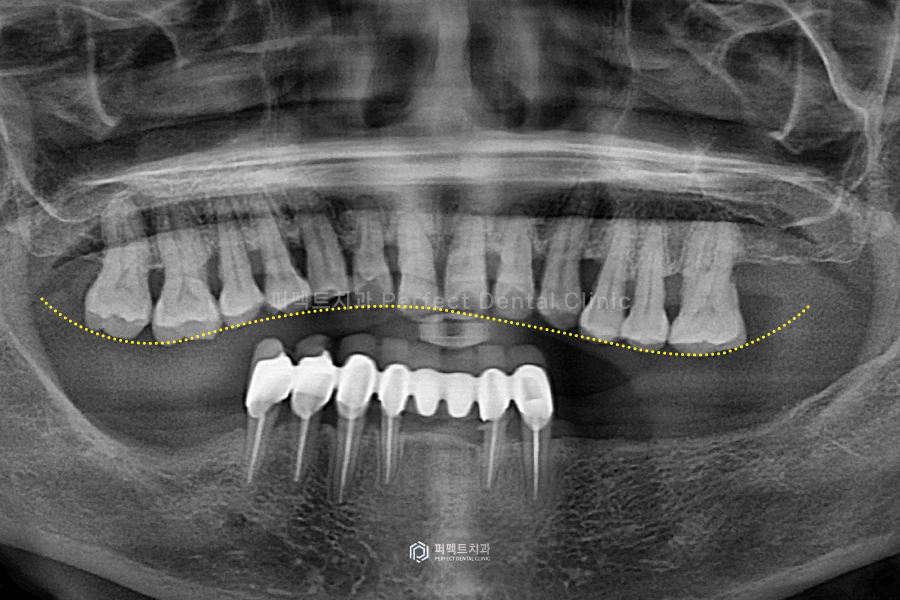

처음 병원에 내원 하셨을 당시 파노라마 엑스레이 사진입니다. 아랫니는 앞니 쪽에만 치아가 있고, 윗니는 왼쪽 어금니 하나를 제외한 전체 치아가 남아있는 상태였습니다.

어금니가 없는 아랫니는 부분틀니를 사용하시고 있는 상황이었는데요. 환자분께서는 아랫니의 경우 부분틀니도 불편하고, 남아있는 아랫니 앞니 부분도 다 흔들린다고 말씀을 하셨고, 윗니 또한 전체적으로 치아가 흔들리고 아프다고 하셨습니다.

한 번 보시면 '교합평면'이 무너져 있는 상황입니다. 치아가 반듯하게 균형이 맞아야 하는데, 아래 어금니가 없어 위 어금니가 아래로 쏟아져 내려와 교합이 무너지게 된 것인데요. 이러한 상태에서 틀니를 제작해서 사용하다보니 균형도 안맞고, 잘못된 힘을 계속 받게 된 것 입니다.